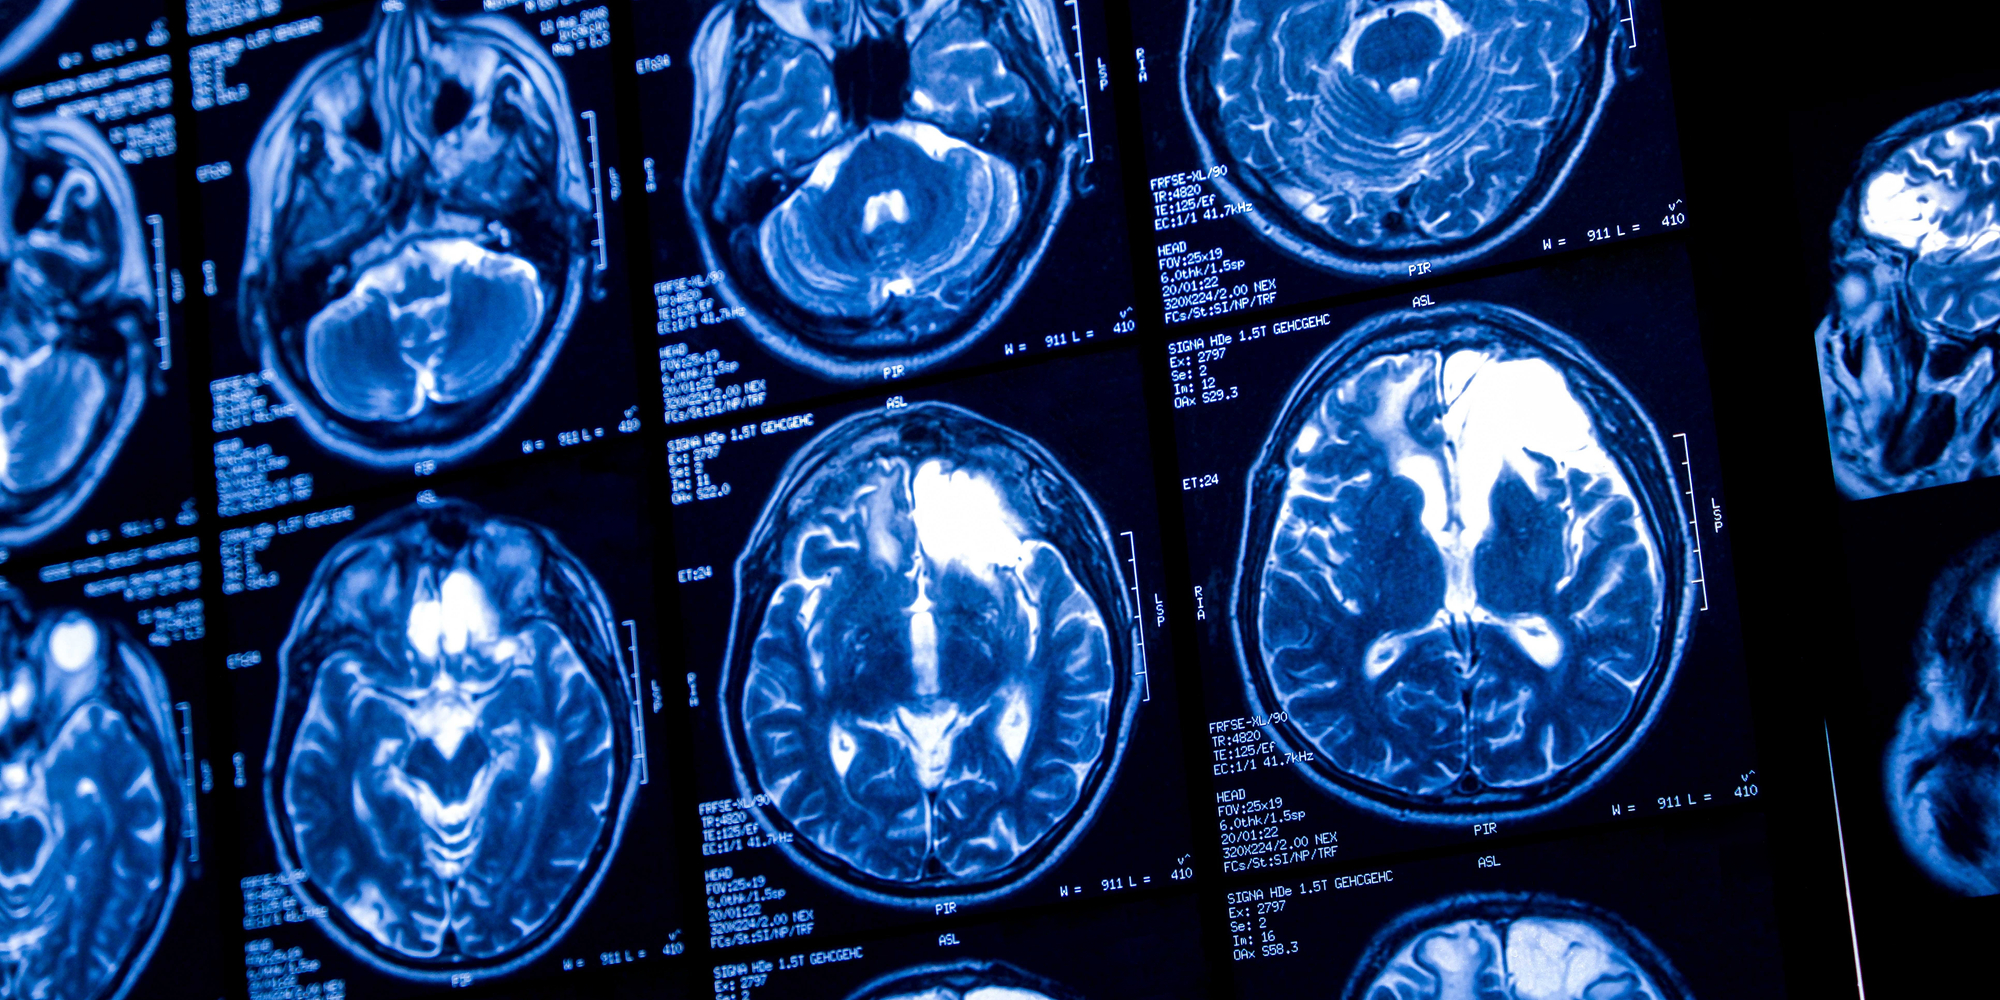

A brain tumor diagnosis can be scary. But at the OSF HealthCare Illinois Neurological Institute Brain Tumor Center, you are not alone. We prioritize quick and precise imaging to identify your specific type of brain tumor, so we know exactly how to treat it.